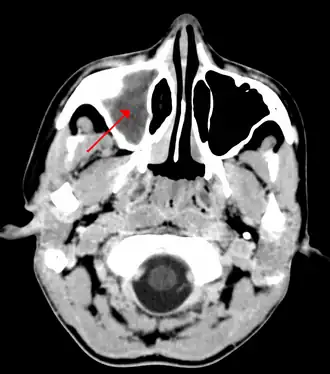

Kaakholte-ontsteking. De sinus maxillaris (rode pijl) is licht gekleurd door ontstoken slijmvlies en vocht in de holte. Normaal zijn de holten op de foto donkerder dan het omgevende bot omdat er lucht in zit. | ||||

Sinusitis of bijholteontsteking is een aandoening die veroorzaakt wordt door bacteriën, virussen of soms een allergie in de slijmvliezen van de neusbijholten. Dikwijls als gevolg van een verkoudheid zijn de bijholten, die door kanaaltjes in verbinding staan met de neus, gevuld met dik slijm. Het neusslijmvlies is ontstoken en dus gezwollen. Hierdoor kan het slijm en/of pus niet goed weglopen. Het gevolg hiervan is een pijnlijk en drukkend gevoel aan de bovenkant van het gelaat, en rond de ogen. Bij voorover bukken kan het drukkende gevoel toenemen. Ook is er soms sprake van hoofdpijn. In zeldzame gevallen is het mogelijk dat er een dentogene vorm van sinusitis ontstaat: pijn in deel van het bovengebit waarvoor geen tandheelkundige verklaring gevonden wordt. De aandoening komt vooral veel voor bij volwassenen. Bij kinderen tot 8 jaar nooit, de kaakholte is dan wegens de aanwezigheid van het wisselgebit nog niet voldoende ontwikkeld.

In zeldzame gevallen kan een sinusitis een chronisch karakter krijgen. Leegzuigen van de holten kan dan nodig gevonden worden. Een kno-arts kan met een CT-scan van het hoofd goed zien waar de problemen zich voordoen. Ook kan een scheef neustussenschot de reiniging van de holtes belemmeren met een verhoogde kans op een bijholteontsteking tijdens een verkoudheid. Meestal gaat een sinusitis echter vanzelf over.